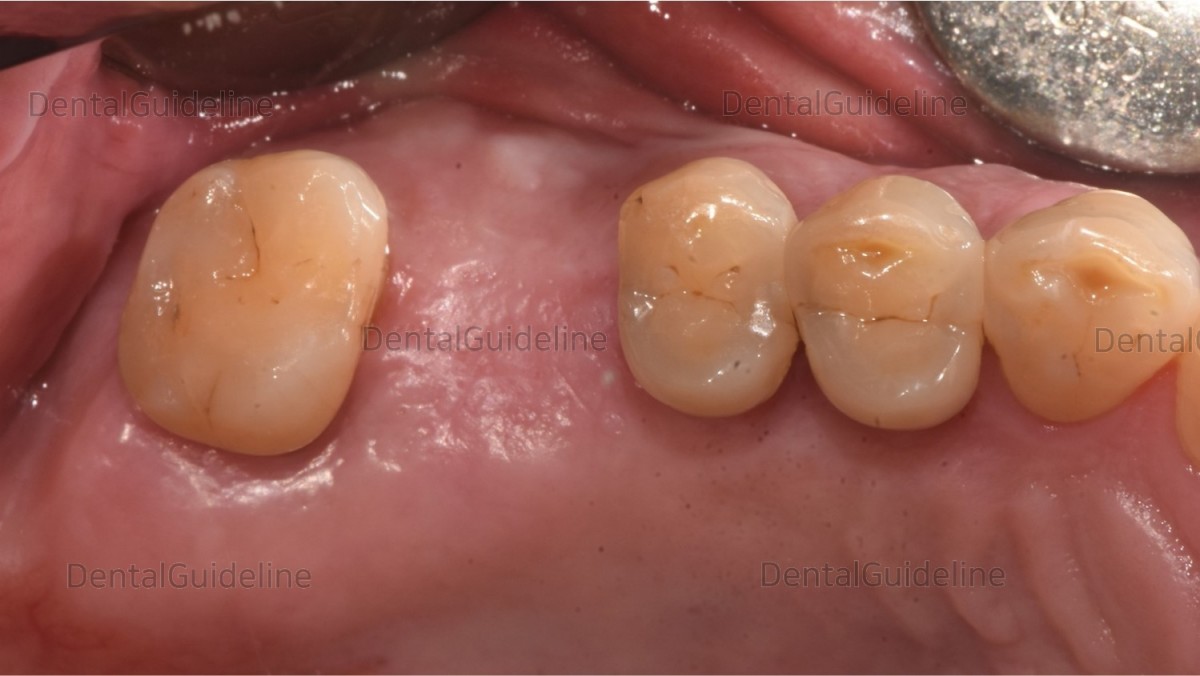

5. 10 weeks after implant placement. On the day of the second surgery.

![]()